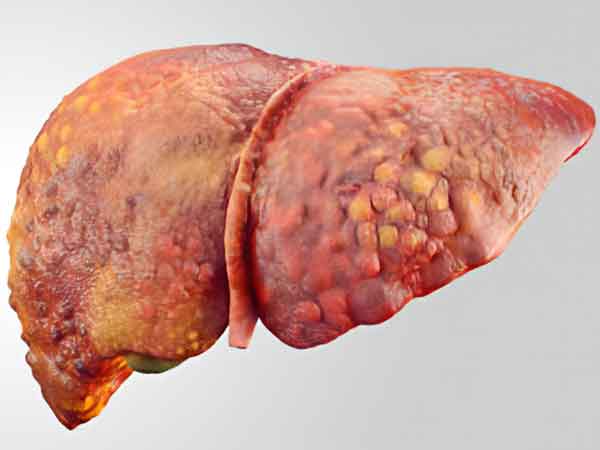

درمان سرطان کبد و تجویز استاد بنی هاشمی

متن سوال درمان سرطان کبد: برای بیمار ۷۷ ساله که سرطان کبد دارند و کل بدن متاستاز کرده است، روش های طب سنتی تا حدودی انجام شده است، رنگ پوست و چشم زرد است و ورم پا دارند افت قند و فشار خون و ضعف پا دارند چه پیشنهادی برای درمان دارید؟